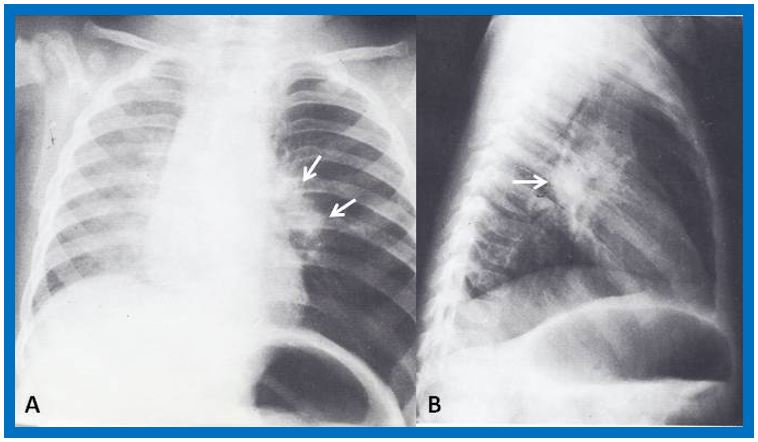

Electrocardiogram (ECG) (Figure 6) and the vectorcardiogram (not shown) revealed right atrial and ventricular hypertrophy. Chest roentgenogram (Figure 7) showed moderate cardiomegaly and prominent main pulmonary artery (PA) segment and clear lung fields. Lung scan with 131I-labeled macro-aggregated albumin was suggestive of multiple pulmonary emboli. Blood gas analysis showed pH 7.56; PaO2 80 mmHg, PaCO2 23 mmHg and bicarbonate 24 mEq/liter. Routine pulmonary function studies revealed restrictive lung disease. The ratio of wasted ventilatory volume (physiological dead space) to tidal volume (VD:VT) using Bohr's equation was 0.58 (normal 0.3 or less).